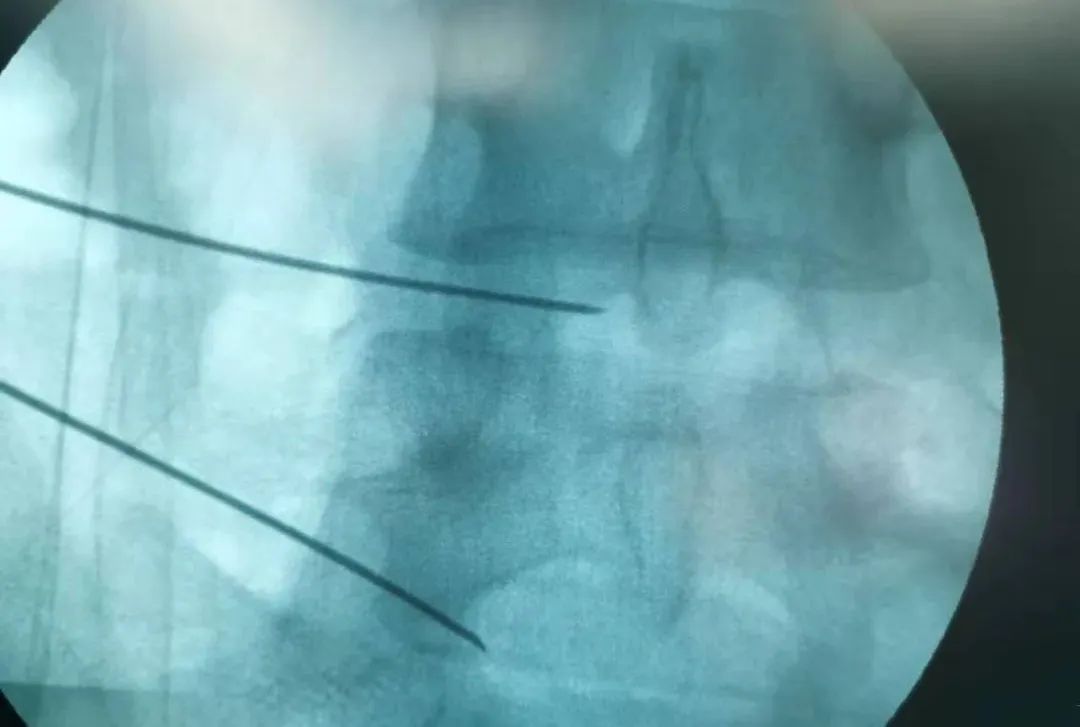

2022年3月15日上午,赵学刚主任为其成功实施了经皮穿刺腰椎间盘射频消融术,手术顺利,术后症状消失,患者自行走回病区。

赵学刚主任为其成功实施了经皮穿刺腰椎间盘射频消融术

经皮穿刺腰椎间盘射频消融术

是一种腰椎微创脊柱介入方法

通过专用射频针经过腰椎皮肤

主要从侧方进入椎间盘

进入椎间盘方法

一般需要在C臂机监视下

准确达到椎间盘突出的靶点部位

即突出部位

通过专用射频针

直达突出部位